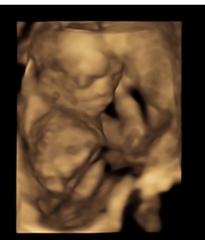

Birthmark on 4D ultrasound??

I had a 4D scan the other day and think I can see a large mole on my baby’s cheek, is that something that can be seen in a 4D scan? Should I be worried?